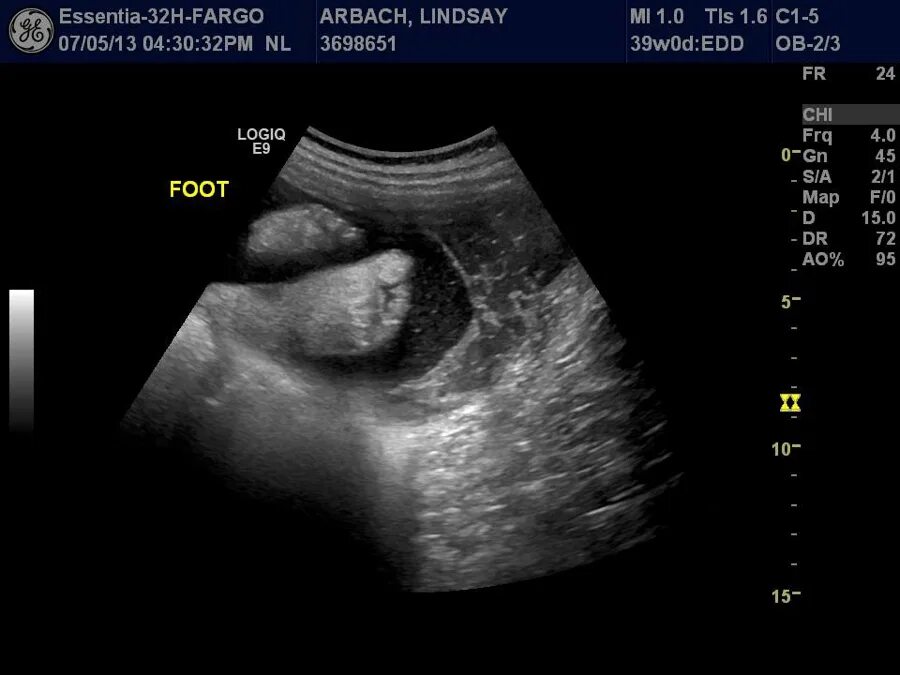

38 3 недель беременности